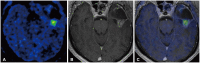

The imaging and clinical management of patients with brain tumor continue to evolve over time and now heavily rely on physiologic imaging in addition to high-resolution structural imaging. Imaging remains a powerful noninvasive tool to positively impact the management of patients with brain tumor. This article provides an overview of the current state-of-the art clinical brain tumor imaging. In this review, we discuss general magnetic resonance (MR) imaging methods and their application to the diagnosis of, treatment planning and navigation, and disease monitoring in patients with brain tumor. We review the strengths, limitations, and pitfalls of structural imaging, diffusion-weighted imaging techniques, MR spectroscopy, perfusion imaging, positron emission tomography/MR, and functional imaging. Overall this review provides a basis for understudying the role of modern imaging in the care of brain tumor patients.